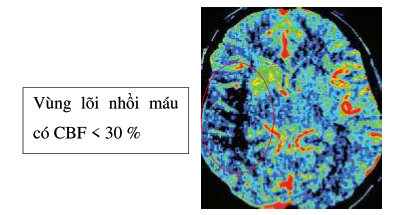

- CLVT tưới máu não: tính các thể tích lõi nhồi máu và vùng tranh tối tranh sáng nhằm mở rộng cửa sổ điều trị tái thông mạch.

- Chụp cộng hưởng từ tưới máu não: tính các thể tích lõi nhồi máu và vùng tranh tối tranh sáng nhằm mở rộng cửa sổ điều trị tái thông mạch.